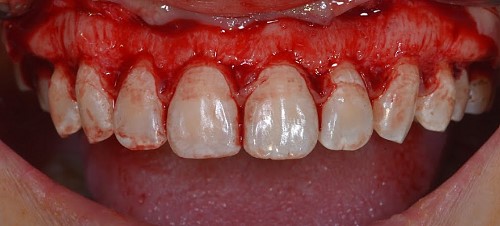

The STL files of the maxilla and teeth were manipulated using BlueSky Plan software (see Fig. 8). Subsequently, a guide was designed to facilitate osseous resection, adapting to both the teeth and the maxilla (see Fig. 9). In the surgical phase, a full-thickness flap was raised in the upper jaw, and the guide was affixed (see Figs 10 and 11). The guide snugly conformed to the bone, and its position was verified with a margin distance from CEJ set at 3 mm (see Figs 12 and 13). Postoperative results at 2 and 12 months are shown in Figs 14 and 15. The final outcomes closely resembled the Digital Smile Design (DSD) simulation conducted before treatment (see Fig. 16).